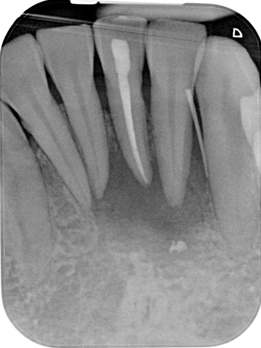

Pre-Operative Radiograph Tooth 31

- Large periapical radiolucency measuring 12.4mm at the widest width.

- Perforation of buccal bone

- Lesion involving apex of 32 and 41 (adjacent teeth)